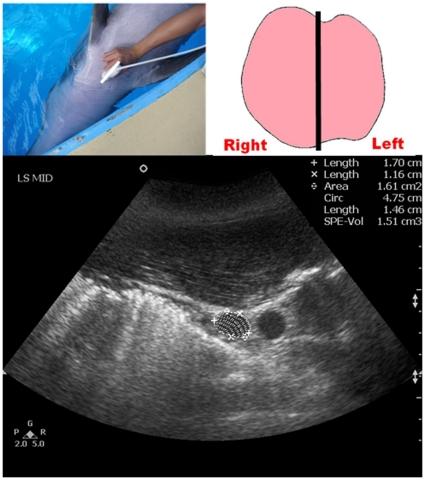

A comparison of portable ultrasound and fully-equipped clinical ultrasound unit in the thyroid size measurement of the Indo-Pacific bottlenose dolphin.

Measurement of thyroid size and volume is a useful clinical parameter in both human and veterinary medicine, particularly for diagnosing thyroid diseases and guiding corrective therapy. Procuring a fully-equipped clinical ultrasound unit (FCUS) may be difficult in most veterinary settings. The present study evaluated the inter-equipment variability in dolphin thyroid ultrasound measurements between a portable ultrasound unit (PUS) and a FCUS; for both units, repeatability was also assessed. Thyroid ultrasound examinations were performed on 15 apparently healthy bottlenose dolphins with both PUS and FCUS under identical scanning conditions. There was a high level of agreement between the two ultrasound units in dolphin thyroid measurements (ICC = 0.859-0.976). A high intra-operator repeatability in thyroid measurements was found (PUS: ICC = 0.854-0.984, FCUS: ICC = 0.709-0.954). As a conclusion, no substantial inter-equipment variability was found between PUS and FCUS in dolphin thyroid size measurements under identical scanning conditions, supporting further application of PUS for quantitative analyses of dolphin thyroid gland in both research and clinical practices at aquarium settings.

测量甲状腺大小和体积是人类和兽医医学中非常有用的临床参数,特别是用于诊断甲状腺疾病和指导矫正治疗。在大多数兽医环境中,获得功能齐全的临床超声设备(FCUS)可能较为困难。本研究评估了在便携式超声设备(PUS)和 FCUS 之间海豚甲状腺超声测量的设备间变异性;对于这两个设备,还评估了重复性。在相同的扫描条件下,对 15 只明显健康的宽吻海豚进行了 PUS 和 FCUS 的甲状腺超声检查。两种超声设备在海豚甲状腺测量方面具有高度一致性(ICC=0.859-0.976)。在甲状腺测量方面,操作员内的重复性很高(PUS:ICC=0.854-0.984,FCUS:ICC=0.709-0.954)。总之,在相同的扫描条件下,PUS 和 FCUS 之间在海豚甲状腺大小测量方面没有发现实质性的设备间变异性,支持在水族馆环境中进一步应用 PUS 进行海豚甲状腺的定量分析,无论是在研究还是临床实践中。